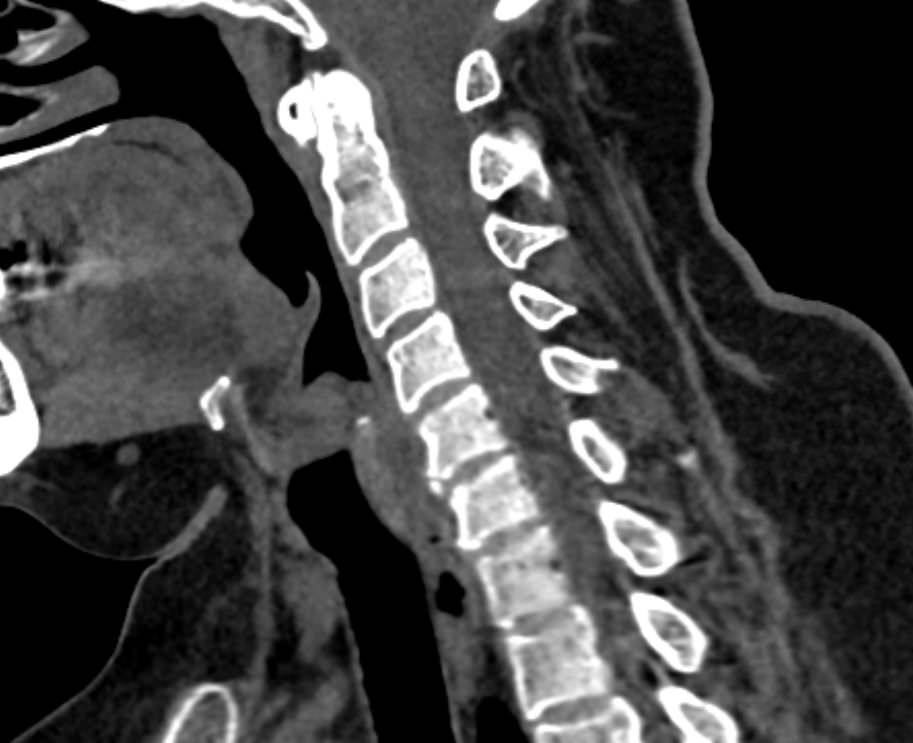

Для диагностики даже незначительных патологических изменений в различных отделах позвоночника, особенно в случае распространенного поражения, применяется один из современных наиболее информативных методов обследования – мультиспиральная компьютерная томография всего позвоночника. Методика основана на использовании проникающей способности рентгеновских лучей через органы и ткани человека и позволяет получить подробное изображение всех структур позвоночного столба. В комплексное обследование входит исследование шейного, грудного, пояснично-крестцового отделов позвоночника и копчика.

В медицинских центрах «Доступная медицина» сканирование всего позвоночника выполняется на новейших мультиспиральных компьютерных томографах последнего поколения TOSHIBA AQUILION в различных модификациях. Особенностью данных аппаратов является их способность проводить от 64 до 128 тончайших срезов одномоментно с минимальной толщиной от 0,5 мм.

Увеличенное количество высокочувствительных детекторов, которыми оснащены томографы, позволяет получать послойные снимки высокого качества с большой скоростью. Эта особенность данных аппаратов обеспечивает быстроту выполнения сканирования. При этом пациент получает минимальную дозу облучения, что имеет важное значение, особенно при такой обширной зоне исследования, как позвоночный столб.